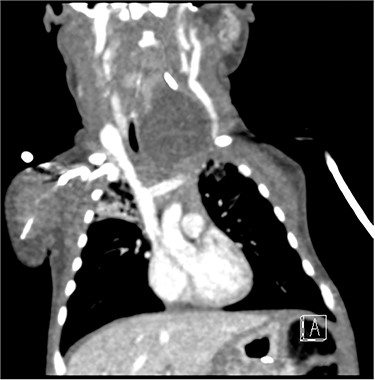

The patient underwent a computed tomography (CT) scan that illustrated a large left-sided supraglottic cyst (3.5 × 2.4 × 2.9 cm) extending from C3 to C7 with paratracheal extension (Figs 1–3). This was confirmed on microlaryngobronchoscopy (MLB) and the cyst was drained. The patient was managed postoperatively in the paediatric intensive care unit where she remained intubated. Extubation was unsuccessful, secondary to worsening stridor and increased work of breathing; a chest X-ray revealed a collapsed right lung. A second MLB was performed and thick bronchial secretions were found, as well as subglottic inflammation, in keeping with a diagnosis of tracheitis.